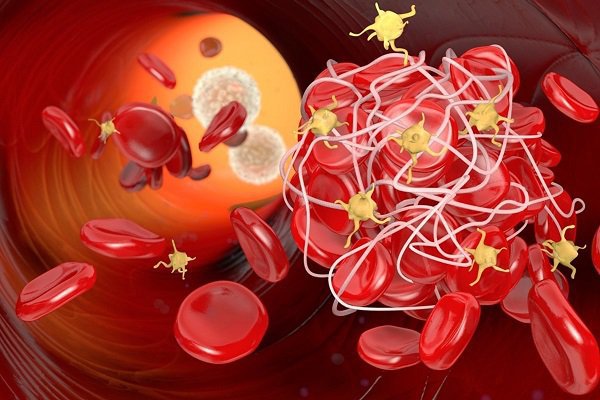

Edoxaban là thành viên của nhóm thuốc chống đông máu Novel (NOACs), và là một chất ức chế Xa có tác dụng chọn lọc, uống, yếu tố chọn lọc. Bằng cách ức chế yếu tố Xa, một protein chủ chốt trong dòng đông máu, edoxaban ngăn chặn sự khuếch đại từng bước của các yếu tố protein cần thiết để hình thành cục máu đông.

Edoxaban giúp ngăn ngừa hình thành cục máu đông bằng cách ngăn chặn yếu tố chất Xa. Đây là một yếu tố đông máu cần thiết để máu đông. Khi một loại thuốc như edoxaban ngăn chặn yếu tố Xa, nó sẽ làm giảm số lượng của một loại enzym gọi là thrombin. Thrombin là một chất cần thiết trong máu để hình thành cục máu đông. Thrombin cũng làm cho các tiểu cầu trong máu của bạn kết dính với nhau, gây ra các cục máu đông. Khi thrombin giảm, điều này sẽ ngăn hình thành cục máu đông (huyết khối) trong cơ thể.

Với rung nhĩ, một phần của tim không đập theo cách mà nó cần. Điều này có thể dẫn đến hình thành cục máu đông trong tim. Những cục máu đông này có thể di chuyển đến não, gây ra đột quỵ hoặc đến các bộ phận khác của cơ thể. Edoxaban là một loại thuốc làm loãng máu giúp giảm nguy cơ bị đột quỵ bằng cách giúp ngăn ngừa hình thành cục máu đông.